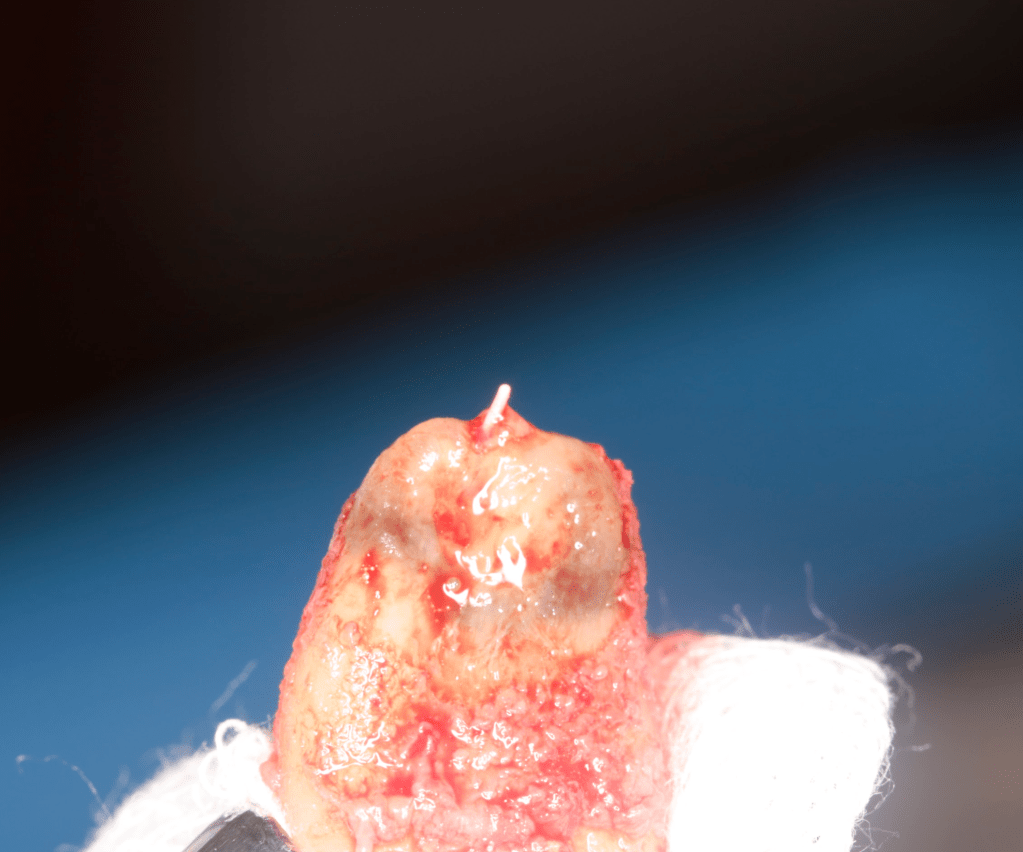

Reimplante, istmo apical, curación cortical palatina 1 año